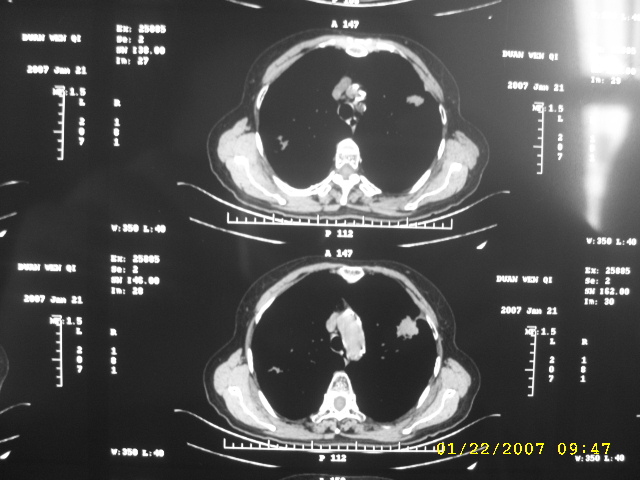

女,75.胸痛。

07.01.21.

1、周围型肺癌。2、慢性支气管炎、肺气肿、肺心病。

明显的不规则形肿块,分叶、短毛刺、胸膜刺激征,血管扭曲征等周围型肺癌的征象明显,应首先考虑周围型肺癌。应与肺多发结核球相鉴别

双侧肺内块状病灶,均见分叶毛刺,左肺见典型胸膜凹陷,双侧双原发癌.